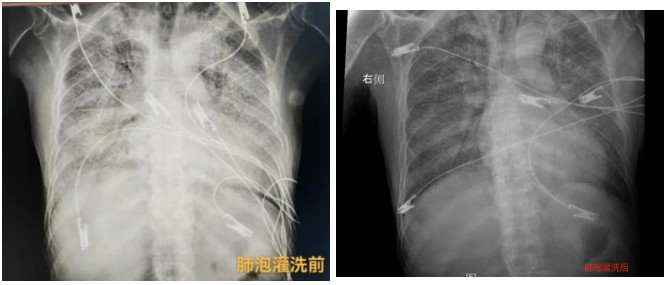

▲肺泡灌洗前(左)和肺泡灌洗后(右)

術后1小時,影像學復查顯示,高先生的肺部情況明顯改善。經過充分評估,先后撤除ECMO、拔除氣管插管。他的神志清楚,對在場的醫(yī)護人員豎起大大的拇指。